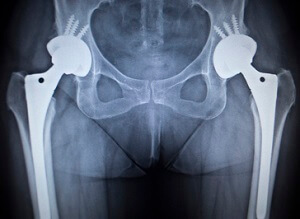

Hip replacement is a surgical procedure in which the damaged hip joint is replaced with a prosthetic implant. X-ray guided hip replacement involves the use of pre-operative radiographic studies to help select the right size of the implant and to determine the proper position in which the implant should be placed.

- The X-rays help in the selection and sizing of the implants based on your anatomy and can be used to identify anatomical landmarks that serve as reference points so that the prosthesis is implanted in the correct position.

- Special surgical instruments are introduced into the hip and based on the anatomic landmarks identified on the X-rays, the damaged tissue is removed and your surgeon will make precise cuts in your bone to place the implant components in the desired position.